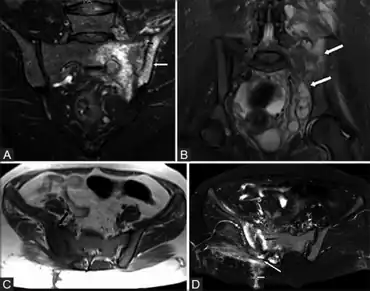

| Magnetic resonance images of sacroiliac joints. Shown are T1-weighted semi-coronal magnetic resonance images through the sacroiliac joints (a) before and (b) after intravenous contrast injection. Enhancement is seen at the right sacroiliac joint (arrow, left side of image), indicating active sacroiliitis. This patient had psoriatic arthritis. Sacroiliitis is a condition caused by inflammation within the sacroiliac joint.[1] This joint is located where the base of the spine, known as the sacrum, and the pelvis, known as the ilium, intersect. "Itis" is a Latin term denoting inflammation.[2] | |